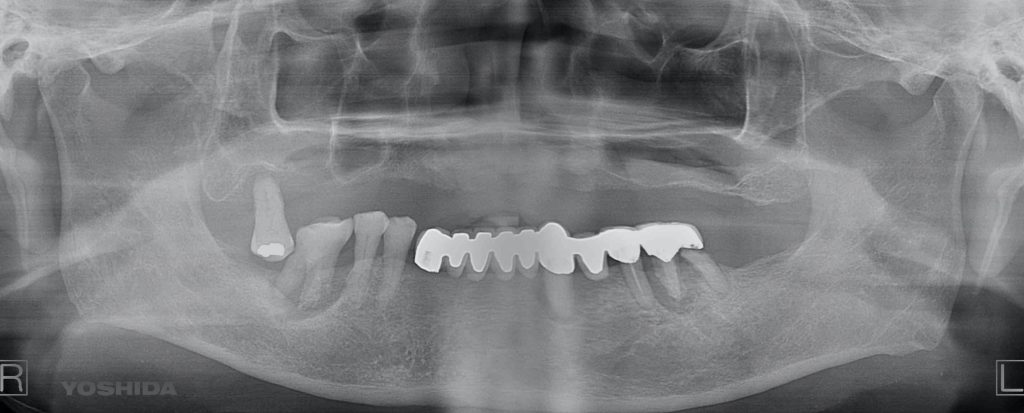

下記の症例は全ての歯を抜歯しなければいけない無歯顎患者さんにインプラントと同時に固定式の歯を装着する事ができる治療方法で最小本数である4本のインプラントで12本分の歯を支える形になり、費用を抑え、最小限のインプラント本数でQOLの回復を劇的に高めます。

これをオールオン4と呼びます。